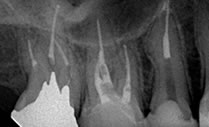

2009年7月

根菅充填より1年経過:来院時にあった根尖の透過像が消失しています。咬合痛もなくなったとのことです。

側枝

近心に側枝があります 。オブチュレーションなら側枝まできれいに根菅充填できます。

RCF

根尖まできれいに充填されています。